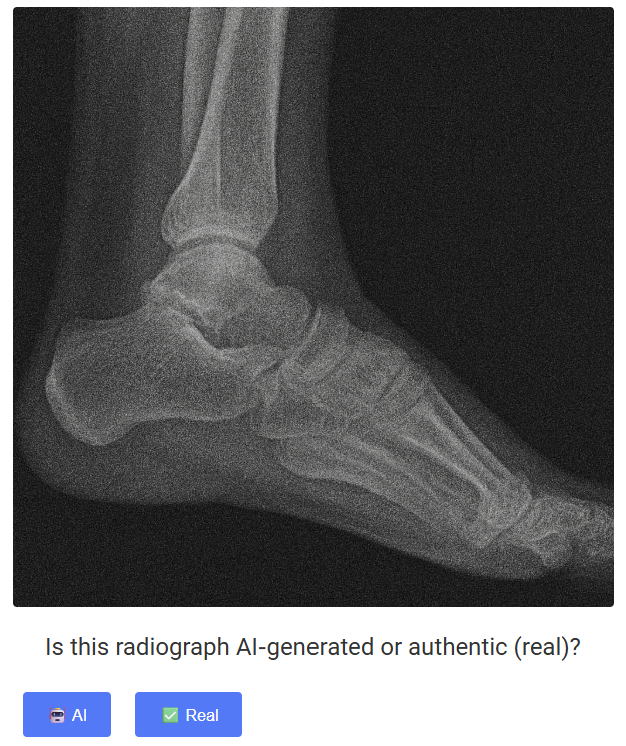

연구팀은 논문과 함께 학습용 딥페이크 X선 데이터 세트도 공개했다. 직접 들어가 진짜 영상과 가짜 영상을 맞춰보면 의료영상 딥페이크가 얼마나 정교한지 체감할 수 있을 것이다.